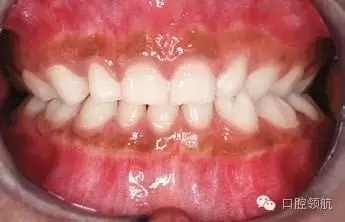

圖2.9中明顯的牙列異常有哪些?

雙側(cè)下頜側(cè)切牙和尖牙移位。

圖2.9